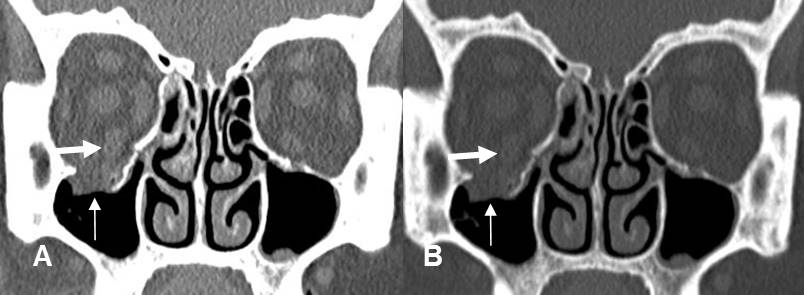

Fig 215 B. Fractura de órbita.

A: TAC coronal en ventana de tejido y B: TAC coronal en ventana de hueso.

Fractura deprimida en el piso de la órbita. Hay herniación de la grasa, pero el recto inferior mantiene su posición. (Flecha gruesa).